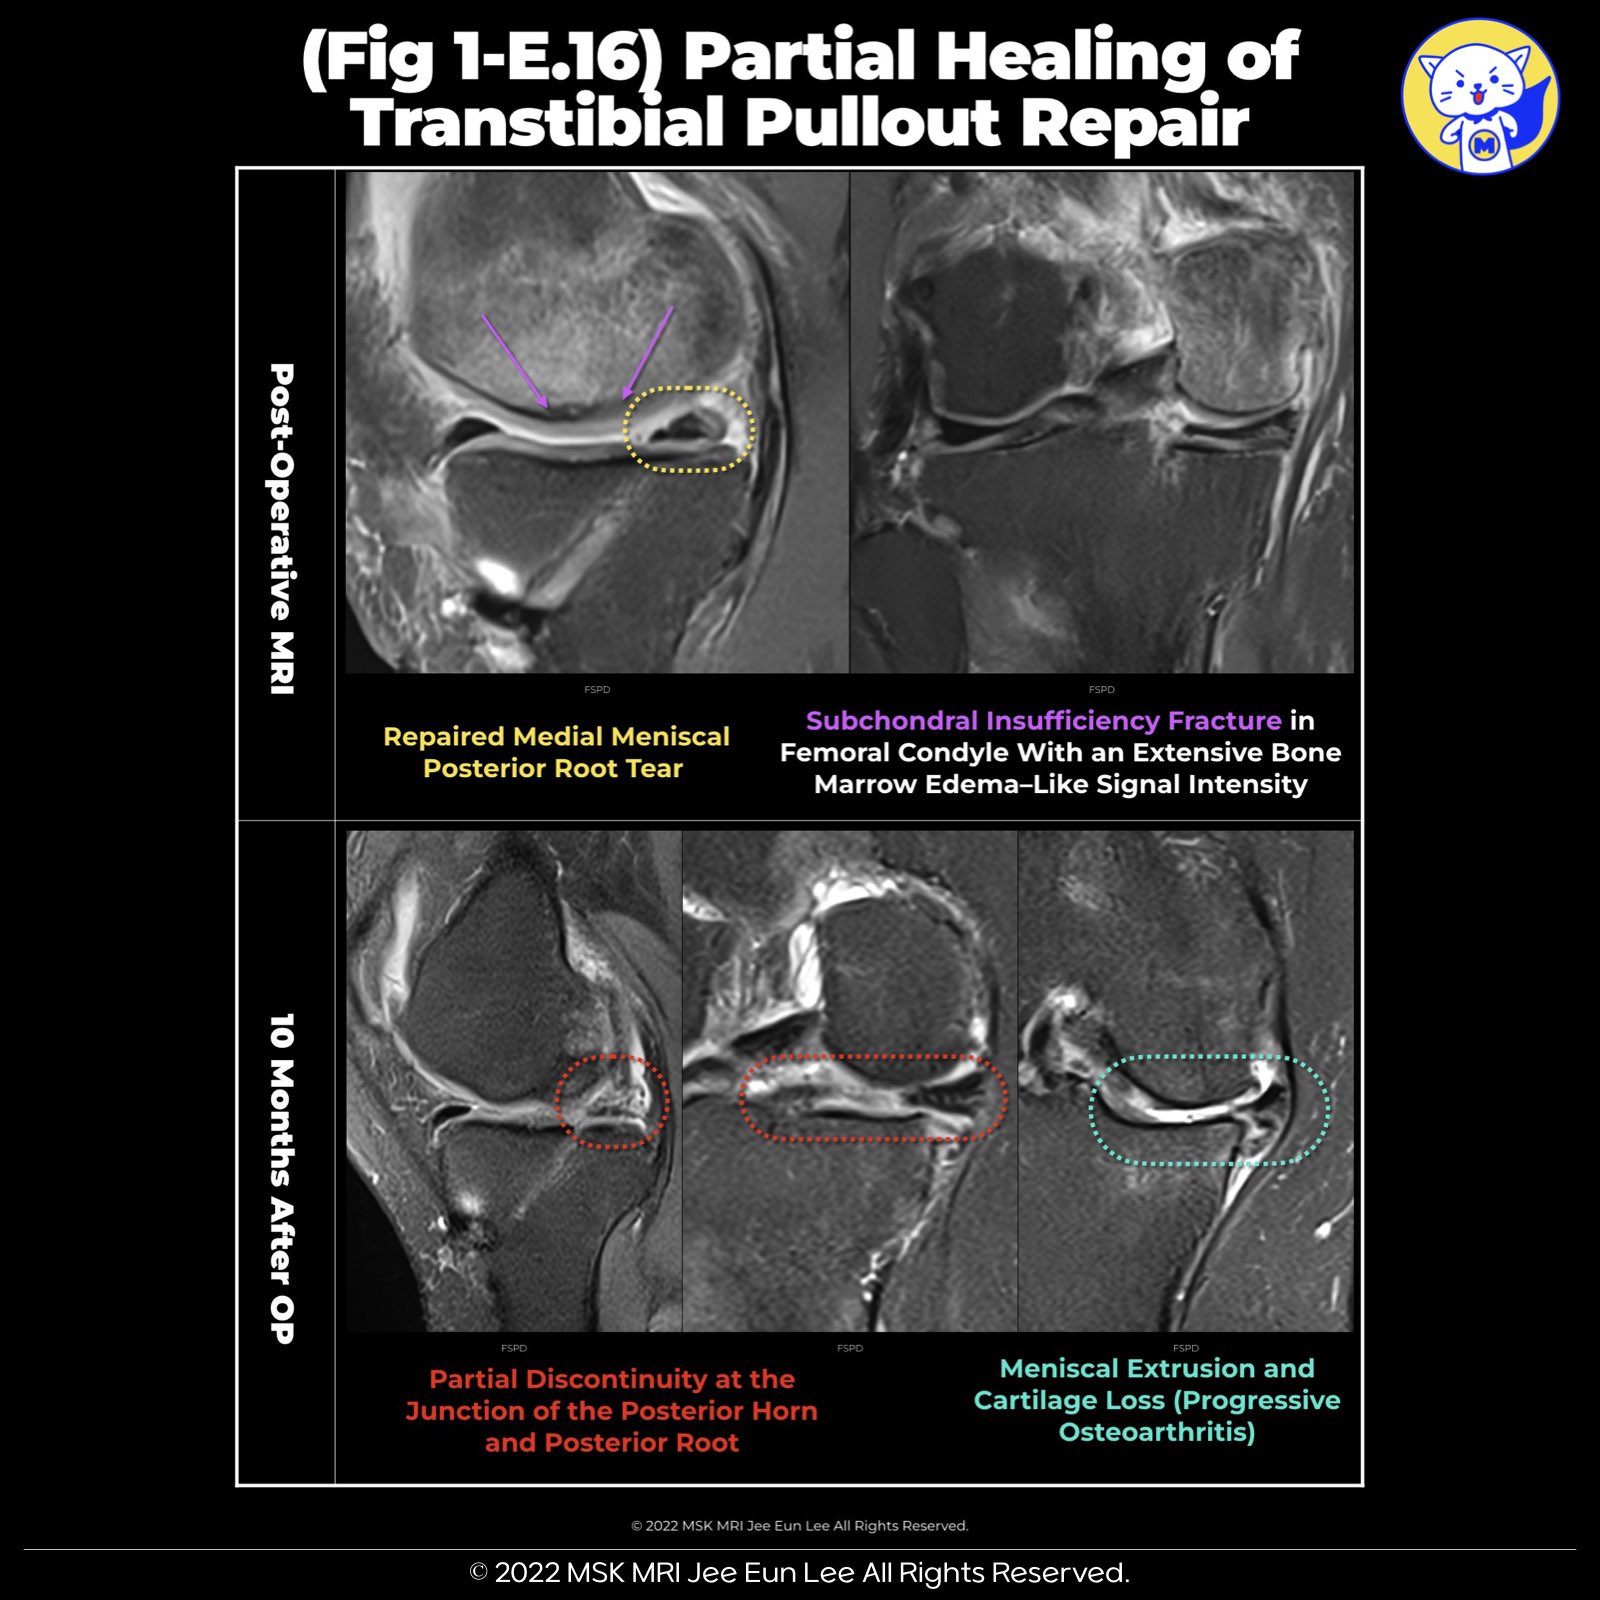

1️⃣ Summary of Meniscal Root Repair Healing Criteria and MRI Interpretation Challenges

• Complete Healing: Defined as the continuity of the repaired meniscal root across axial, coronal, and sagittal planes.

• Partial Healing: Identified when continuity is observed in one or two of these planes.

• Repeat Tear: Recognized by the absence of continuity in all three planes.

2️⃣ MRI Criteria for Repeat Tear:

• Includes root discontinuity and fluid signal intensity in the repaired root. However, such signal abnormalities can also indicate edematous or fibrous scar tissue, not necessarily incomplete healing, especially common in the early postoperative period.

3️⃣ Challenges in MRI Interpretation:

• Increased signal due to edema, cysts, or scar tissue near the repair site can complicate interpretations.

4️⃣ Healing Timeline:

• Complete meniscal healing is generally expected within 4–6 months post-surgery.

• Notably, an intermediate-to-high signal may persist in up to 50% of patients for as long as 12.9 years postoperatively, indicating prolonged healing processes or residual signal changes post-repair.